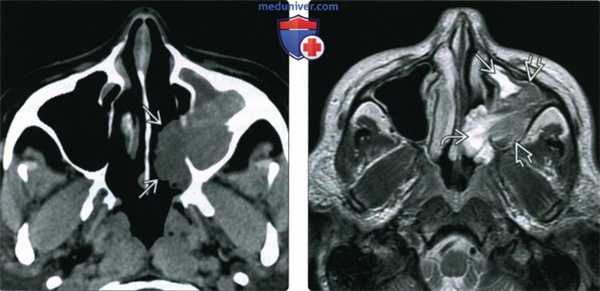

(Слева) При аксиальной КТ без КУ в полости носа слева визуализируется мягкотканное объемное образование со слегка бугристыми краями, распространяющееся в левую верхнечелюстную пазуху. Локализация образования типична для папилломы. При КТ опухоль сложно отличить от «запертого» секрета в пазухе.

(Справа) При аксиальной МРТ Т2 ВИ визуализируется неоднородная инвертированная папиллома, занимающая большую часть верхнечелюстной пазухи. Опухоль гипоинтенсивна в сравнении с секретом, «запертым» спереди и снаружи. Носовой компонент папилломы гиперинтенсивен.